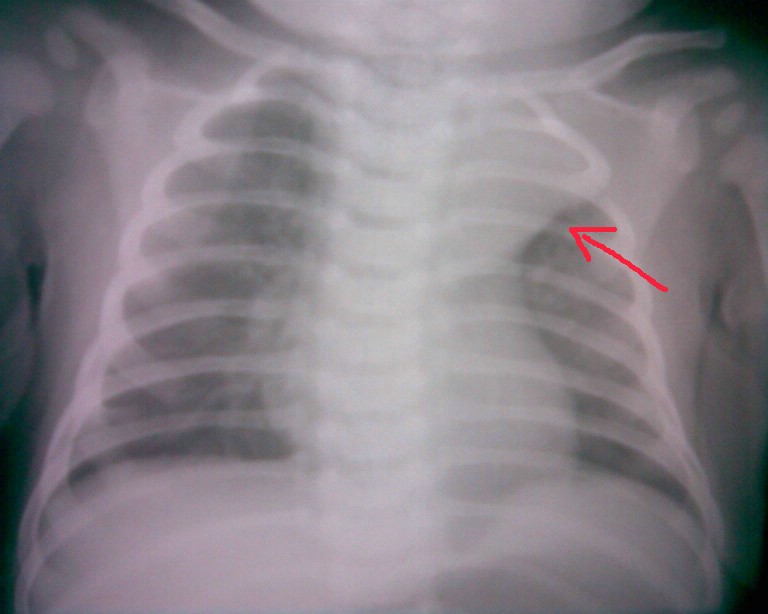

标题: PED0359:男,3月,咳嗽一月。听诊两肺呼吸音粗。帮忙看一

左上肺不张

船帆样得冬冬,只有3个月,考虑是胸腺。

考虑为胸腺,没有肺不张萎缩的征象..

胸腺肥大.体位有点右旋,显得增大胸腺有点象左上肺不张.

建议加照侧位片,如果是上叶肺不张就麻烦了,有支气管异物的可能,还是照了再说吧

左上肺不张,左下肺含气不良,原因待查。